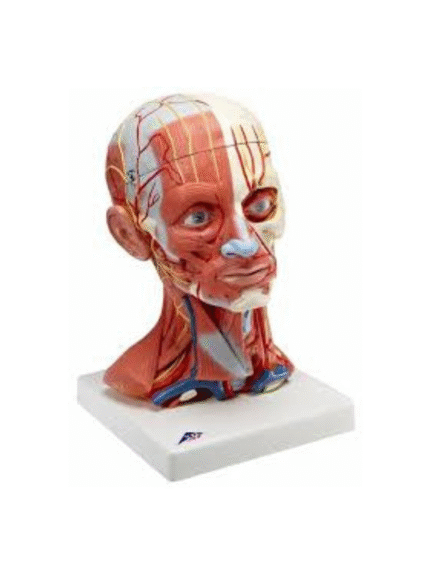

ATL-131 HALF MUSCULAR HEAD WITH VESSEL SOFT

Life size model shows the right half of the human head and neck, sectioned along the sgittal plane. A superficial dissection exposes the facial muscles, the superficial blood vessels and nerve branches of the face and scalp, the parotid and submandibular glands. A median dissection expose the brain with its internal structure, tha pharynx and upper respiratiry tract, a section of the cervical vertebrae.